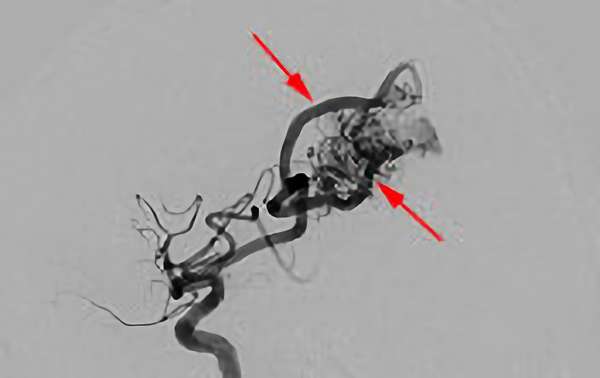

No.1620 手術中